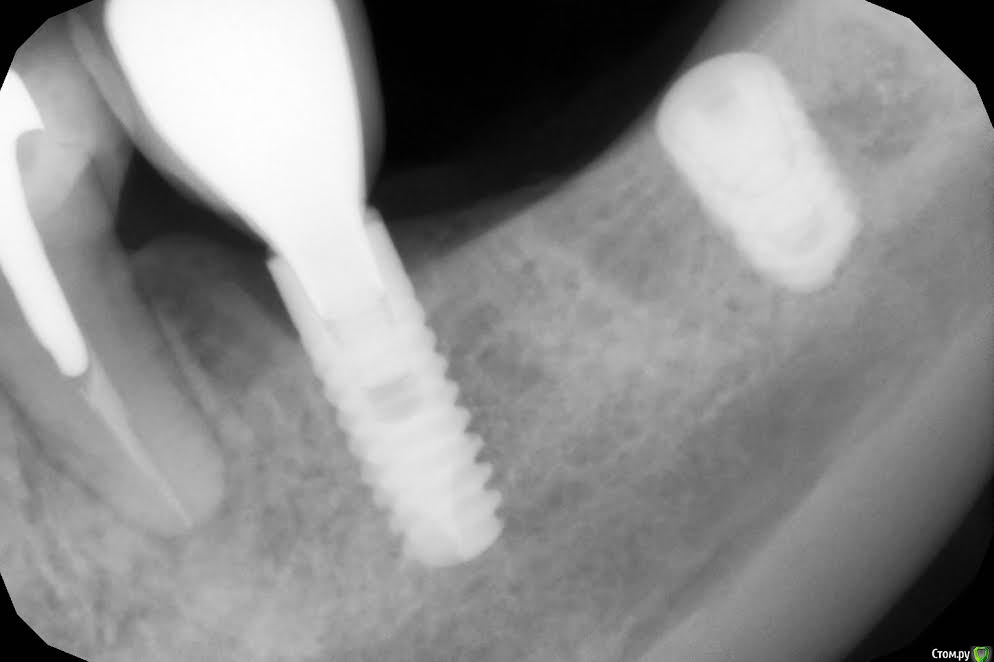

Andre_ Опубликовано 2 июня, 2017 Поделиться Опубликовано 2 июня, 2017 Доброго! Жалобы пациентки - на боли язычно в проекции 3.5, который представлен коронкой на импланте. Жуёт этим более двух лет. Объективно - подвижная слизистая без намёка на прикреплёнку, язычно оголена шея винта на 1,5 - 2 мм. Патологический карман с остатками пищи. Винт стабилен.Ортопед настаивает на демонтаже коронки и имплантопластике. Из вашего опыта - каким способом это лучше сделать, и стоит ли вообще. Может, выкрутить, переставить и раскрыть с десной вместе с рядом стоящим ? Заранее спасибо. Ссылка на комментарий